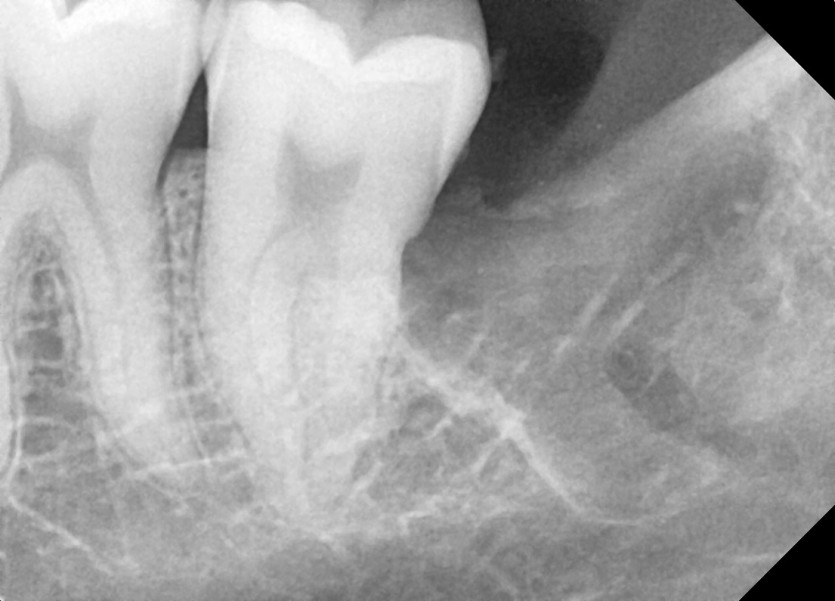

#18,28,38,48 사랑니 발치

구강 외과 전문의가 당일 발치했습니다.